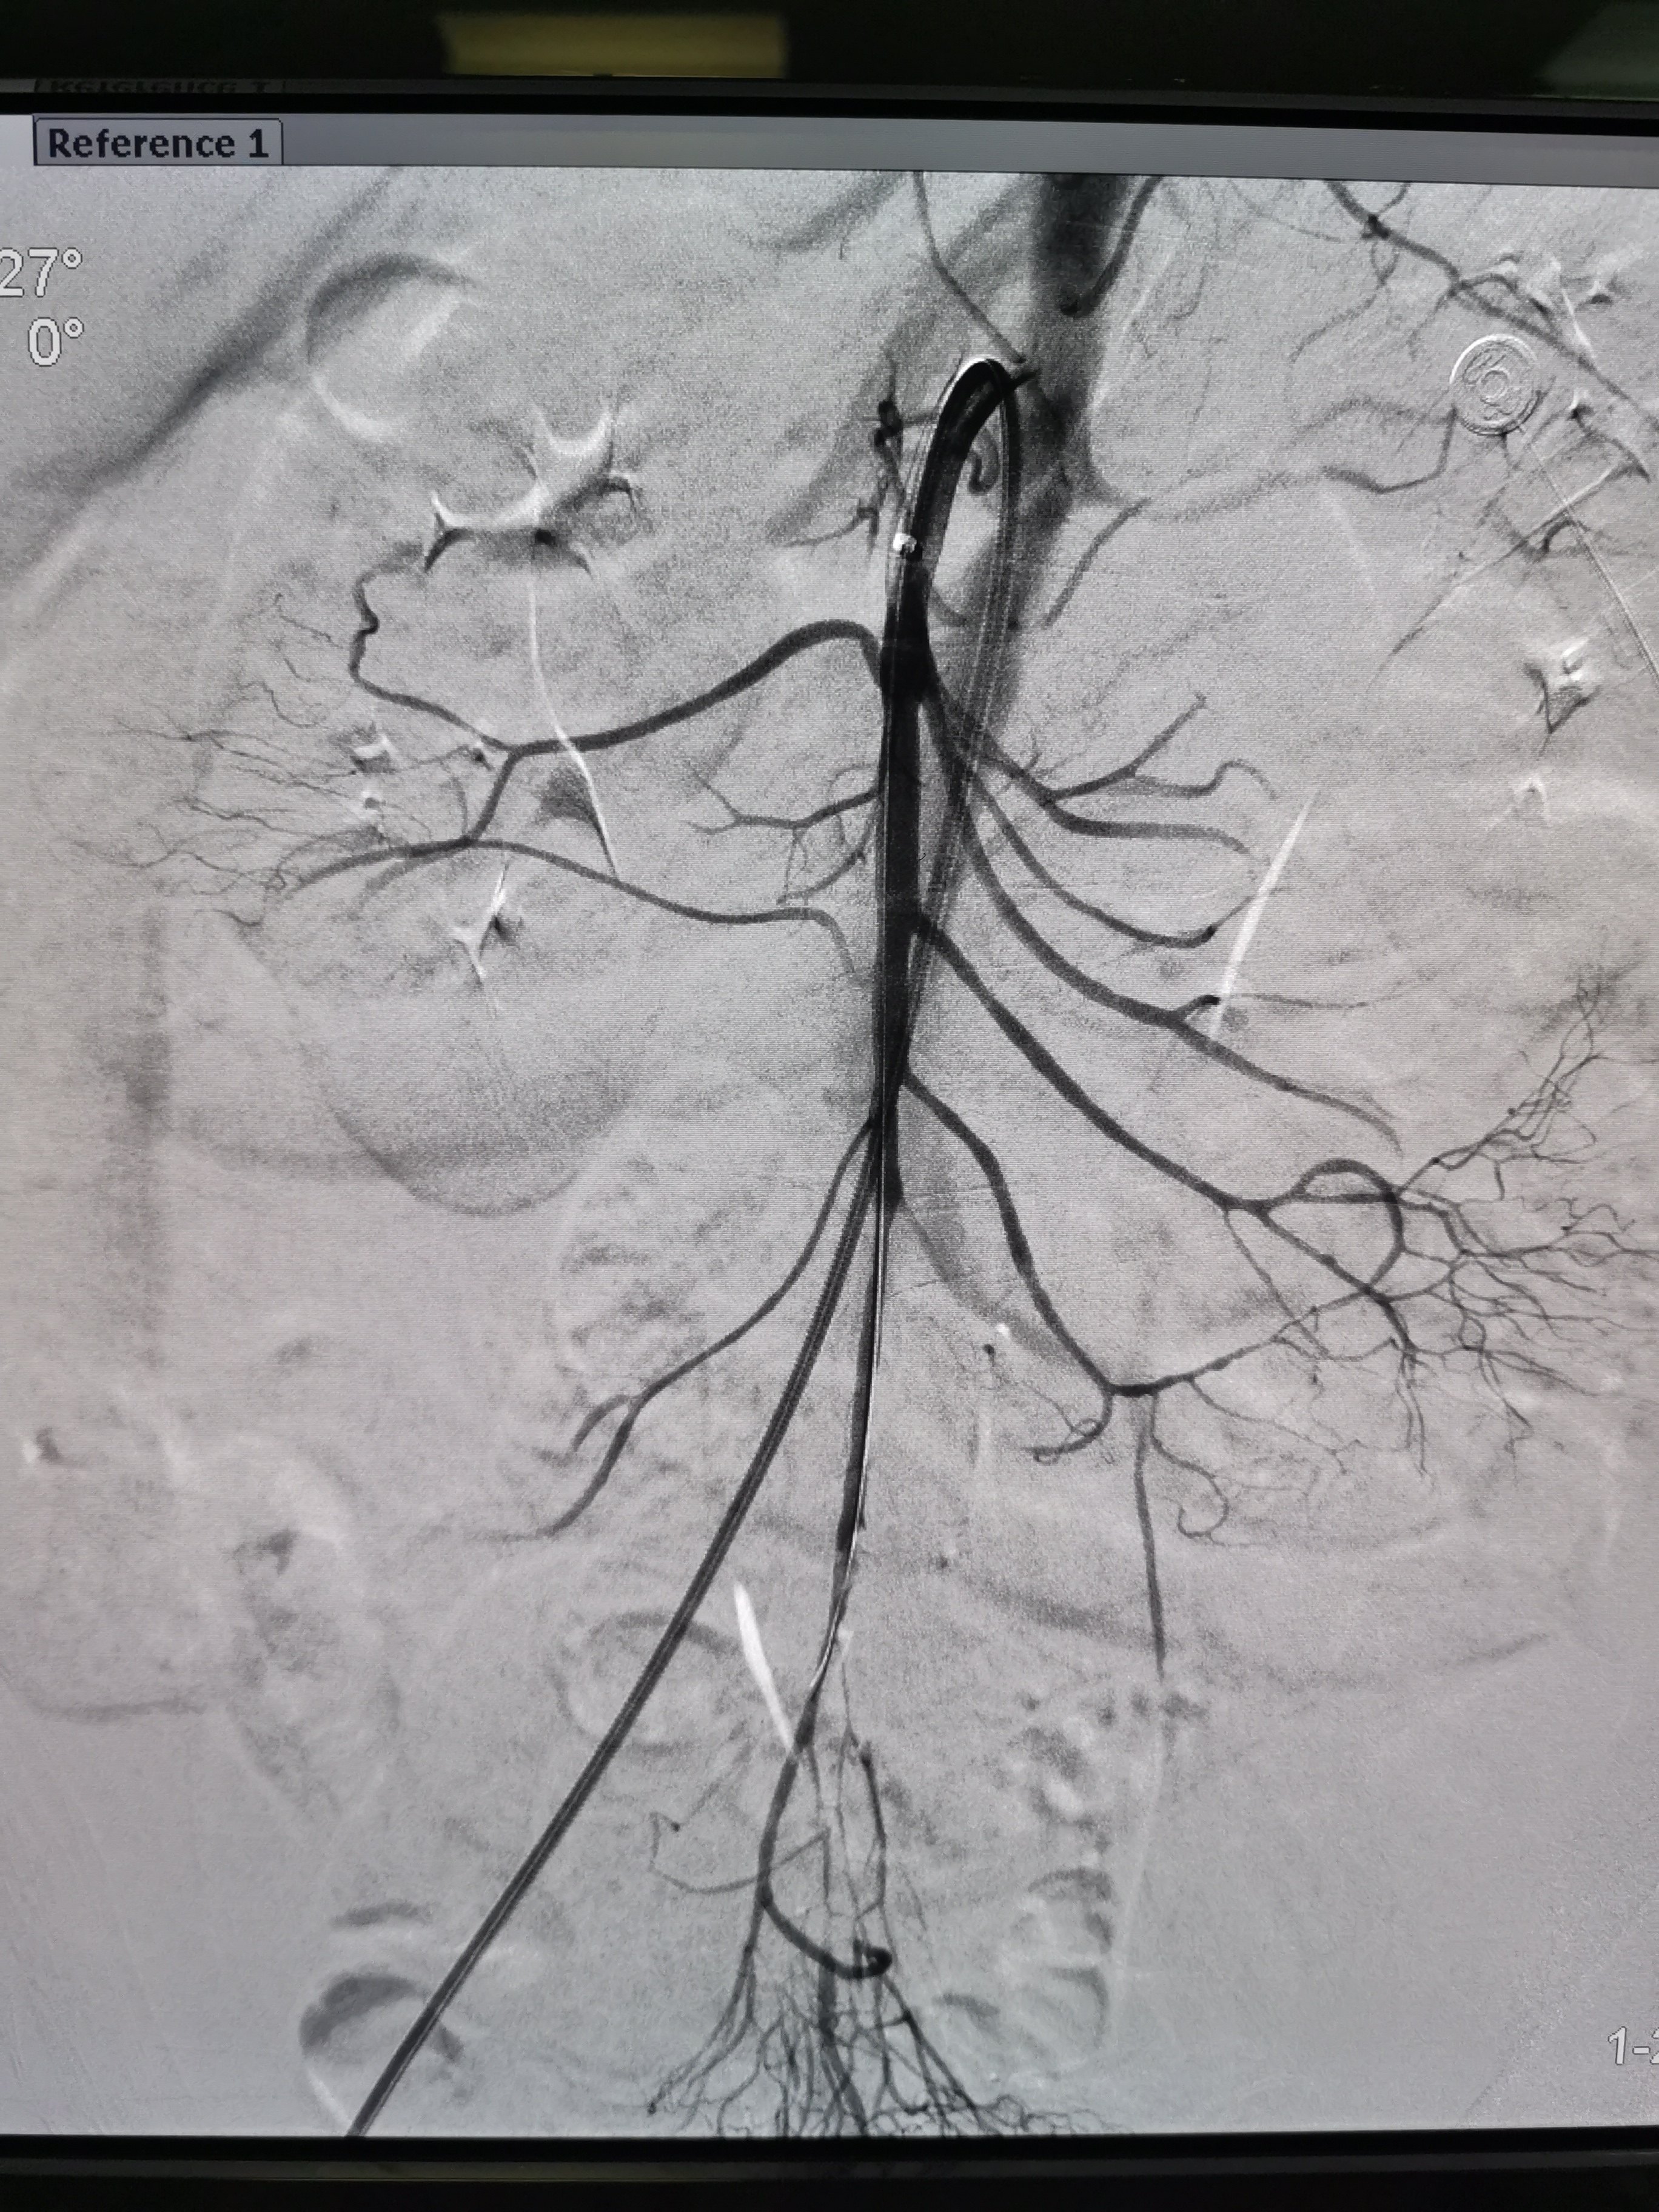

微创治疗急性肠系膜上动脉栓塞 - 好大夫在线

图片尺寸2736x3648